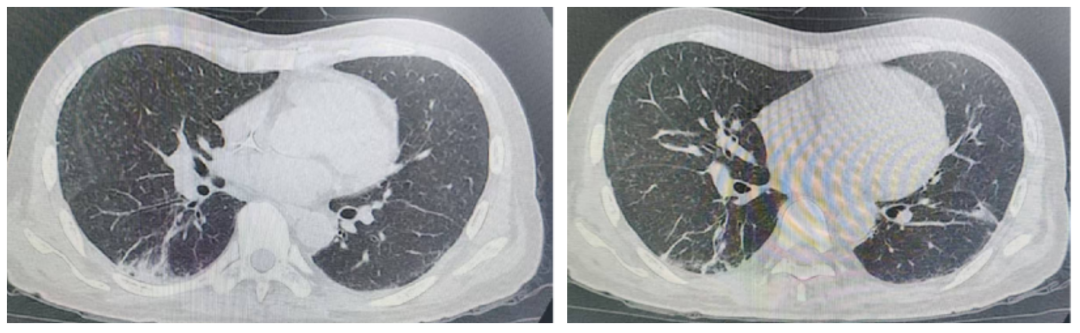

2024-07-24复查胸部CT:双肺炎症较前减少,双下叶实变改善,支气管空气征较前改善,双肺弥漫性支气管树芽征较前明显改善(图4)

图4.2024-07-24胸部HRCT影像